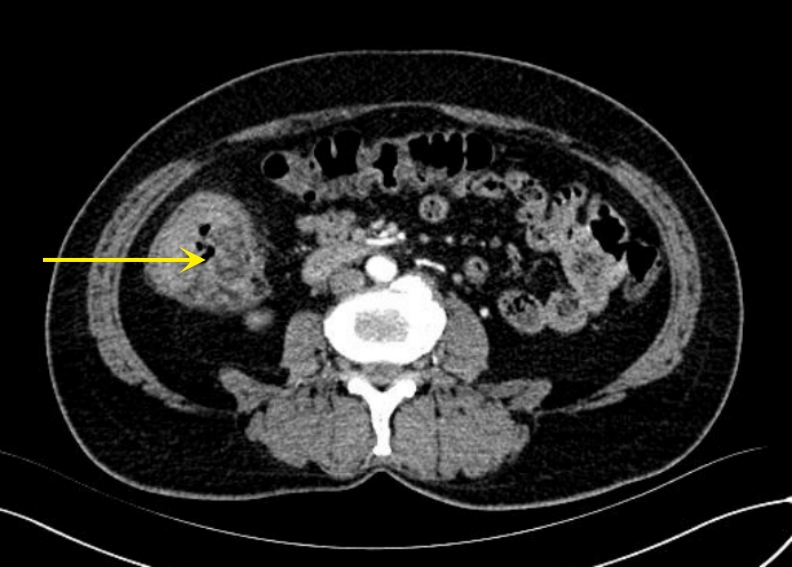

背景与目的 DICER1综合征是一种由DICER1基因胚系突变引起的罕见常染色体显性遗传性肿瘤易感综合征,可累及多器官并表现为多种良恶性肿瘤或增生性病变。肾外肾母细胞瘤、多结节性甲状腺肿及Sertoli-Leydig(S-L)细胞瘤均为其相关表型,但三者同时出现的病例尚未见报道。本文报告1例同时合并上述三种表型的DICER1综合征患者,并结合文献进行分析,以提高对该综合征复杂临床谱系的认识。方法 回顾性分析1例女性患者的临床资料,包括临床表现、影像学检查、手术经过、病理学及免疫组化结果、基因检测及家庭谱系图分析结果;同时检索并总结近30年相关文献,对具有肾母细胞瘤、结节性甲状腺肿及S-L细胞瘤等表型的DICER1综合征病例进行归纳分析。结果 患者9岁时因腹痛行右侧卵巢肿瘤切除术,病理诊断为原发性卵巢畸胎样肾外肾母细胞瘤,术后行辅助化疗。3年后因甲状腺结节行右侧甲状腺切除术,病理为多结节性甲状腺肿。半年后因左侧盆腔新发肿块行卵巢囊肿剥除术,病理提示低分化S-L细胞瘤。基因检测发现DICER1基因外显子8 c.904-1G>C杂合突变,其父亲为同位点杂合突变携带者。结合临床表现及分子遗传学结果,确诊为DICER1综合征。随访3年未见复发或新发病灶。文献复习显示,同时合并上述三种表型的病例尚未见报道。结论 DICER1综合征临床表型多样且诊断具有挑战性。当患儿出现多器官肿瘤或罕见肿瘤组合时,应警惕遗传性肿瘤综合征的可能,尽早开展基因检测及家系筛查。早期识别DICER1综合征对于制定个体化治疗策略及开展长期监测随访具有重要意义。